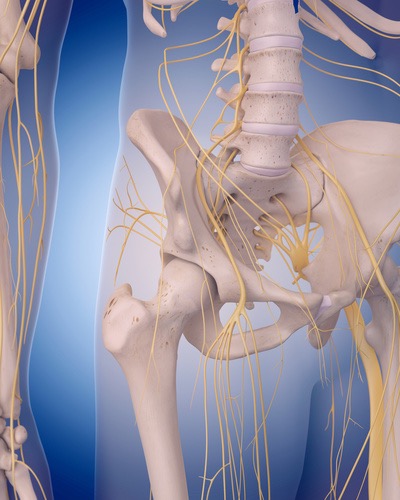

大腿神経はスカルパの三角と呼ばれる鼠径靭帯、内転筋、縫工筋の間にある大腿部の神経です。すぐ近くには大腿動脈や大腿静脈が走行しています。結合組織間の影響を受けやすい部位であるがため、大腿前面のシビレはとてもしぶとい症状のひとつです。ですから筋膜だけのアプローチでは症状改善が乏しく、この大腿神経リリーステクニックがとても効果的な理由でもあります。

坐骨神経痛は殿部~下肢後面に走る痛みとシビレを症状です。ヘルニアや腰部脊柱管狭窄症の疾患でよる表れる症状です。ヘルニアや腰部脊柱管狭窄症の疾患がなくても、例えば梨状筋がこの坐骨神経に刺激を与え神経症状が生じているケースもあります。刺激とは圧迫や滑走性低下による摩擦などを表していますが、坐骨神経とその周囲組織のリリースをすることで今まで取りきれなかった神経痛を解消させることができます。

この坐骨神経痛リリーステクニックを学ぶことであなたは、、、